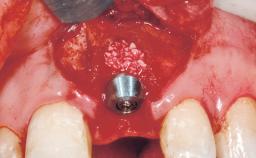

Immediate Flapless Placement of an Implant in a Maxillary Left Central Incisor Site

Type of Implants One-Piece

Placement Protocol Immediate implant placement

Tooth Site Maxillary incisor or canine

Complexity Moderate

Risk of Complications High